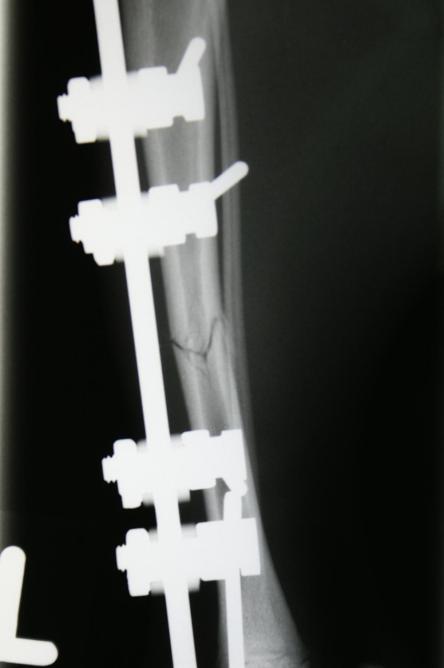

Nach vier Tagen wird nochmals ein Röntgen des Brustkorbs angefertigt, auf welchem erkennbar ist, dass sowohl Lungenblutung als auch Pneumothorax verheilt sind und eine Narkose somit möglich ist. Je zwei Stahlstifte werden ober- und unterhalb der Bruchstelle durch die Haut in den Knochen gebohrt und ausserhalb des Körpers mittels Klampen, Muttern und einem Verbindungsstift verbunden, was zusammen mit der stabilisierenden Wirkung des Wadenbeins eine ausgezeichnete Fixation ergibt. Der ausserhalb der Haut liegende Teil dieser Konstruktion wird mit einem gepolsterten „Verband“ umgeben, damit die Katze mit den Metallteilen nicht an Gegenständen hängen bleibt.

„Pfüdi“ belastet nach der Operation das Bein sofort wieder sehr gut, muss aber zur besseren Heilung 6 Wochen in seiner Bewegung eingeschränkt werden. Nach dieser Zeit wird ein Röntgenbild angefertigt, welches zeigt, dass die Fraktur sehr gut verheilt ist. Der Fixateur Externe wird in einer kurzen Narkose entfernt.

Der Vorteil eines Fixateur Externes ist seine geringe Traumatisierung der Gliedmasse (der Hauptanteil des verwendeten Materials liegt ausserhalb des Körpers, weshalb die Frakturheilung nur minimal beeinträchtigt wird), und es können durch die sehr flexiblen Anordnungsmöglichkeiten von Stiften und Verbindungsstücken auch kompliziertere Splitterfrakturen fixiert werden. Die Montage ist relativ simpel und bedarf nicht einer umfangreichen Ausrüstung.

Als Nachteile sind das Volumen des ausserhalb des Körpers getragenen Gestelles und die Möglichkeit eines Wund- oder Knocheninfektes entlang der durch die Haut reichenden Stifte zu nennen.